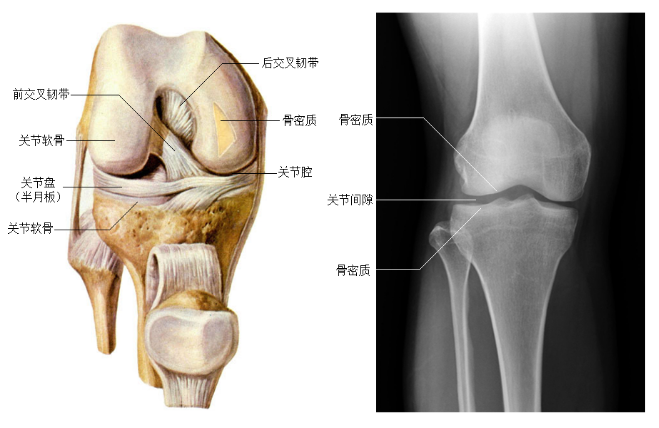

学习“资料”中《下肢骨及其连接》,掌握下肢骨的组成、连接、位置、骨性标志,下肢关节的特点及运动,熟悉下肢骨及其关节的影像解剖学特点。